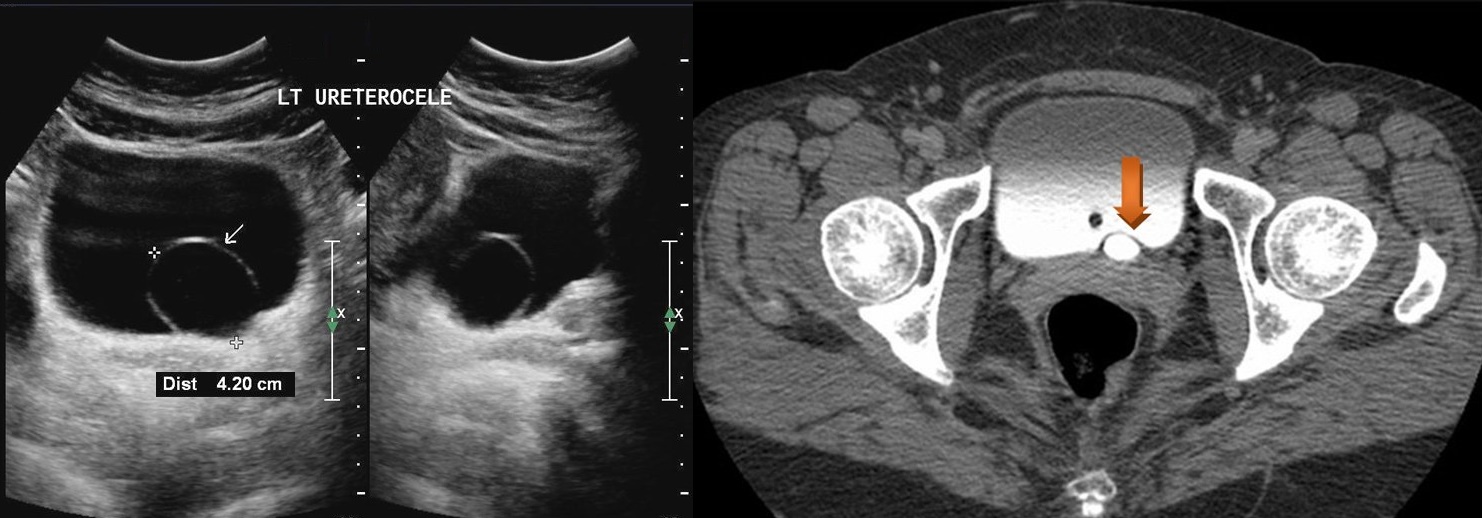

Изображения КТ конкрементов мочевого пузыря